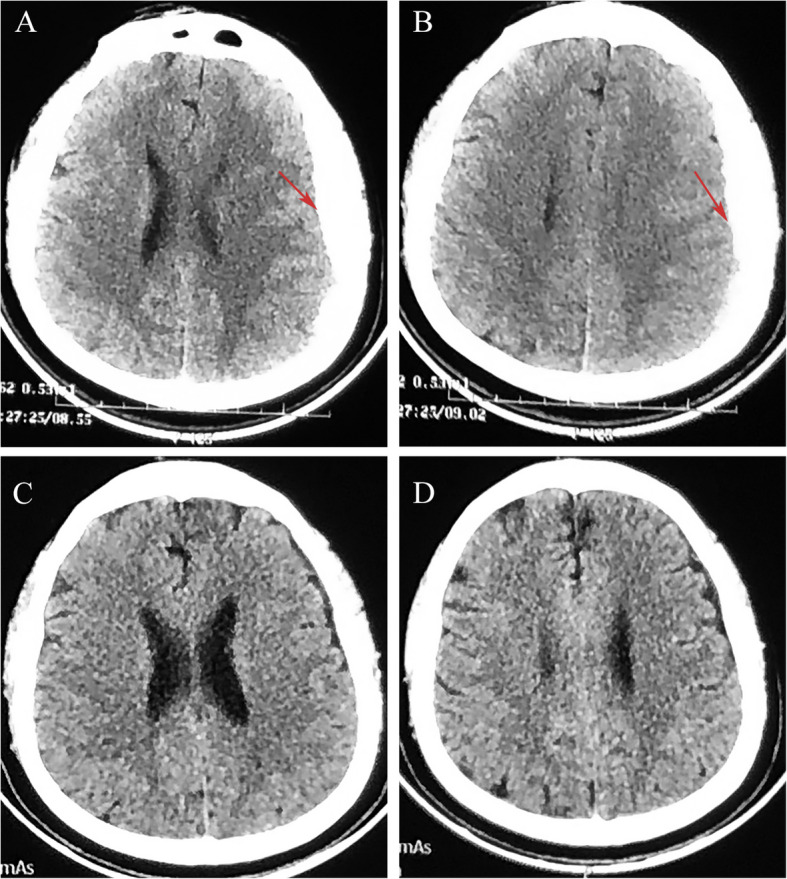

Case presentation: We selected five patients with sASDH who received a treatment regimen of atorvastatin plus low-dose dexamethasone without surgery. We then observed the clinical and radiological features during treatment and follow-up. The PubMed database and Google Scholar were retrieved for literature regarding the efficacy and safety of conservative treatment in patients with ASDH/sASDH. We extracted information including authors, sample size, gender, number of patients (death, poor prognosis, delayed surgery), and risk factors.

Results: Of the five patients, all patients who refused surgery for various reasons were resolved after treatment with atorvastatin plus low-dose dexamethasone for their conditions. No hematomas recurred or progressed during an at least 6-month follow-up. We identified 6 studies after searching the database; a total of 1374 patients (F:M = 3:7) with ASDH/sASDH received initial conservative treatment. The pooled results showed that 13.1% of patients who initially received conservative treatment deteriorated and required delayed surgical treatment. Of 1374, the overall incidence of poor prognosis was 19.2%, and 7% of patients eventually died.